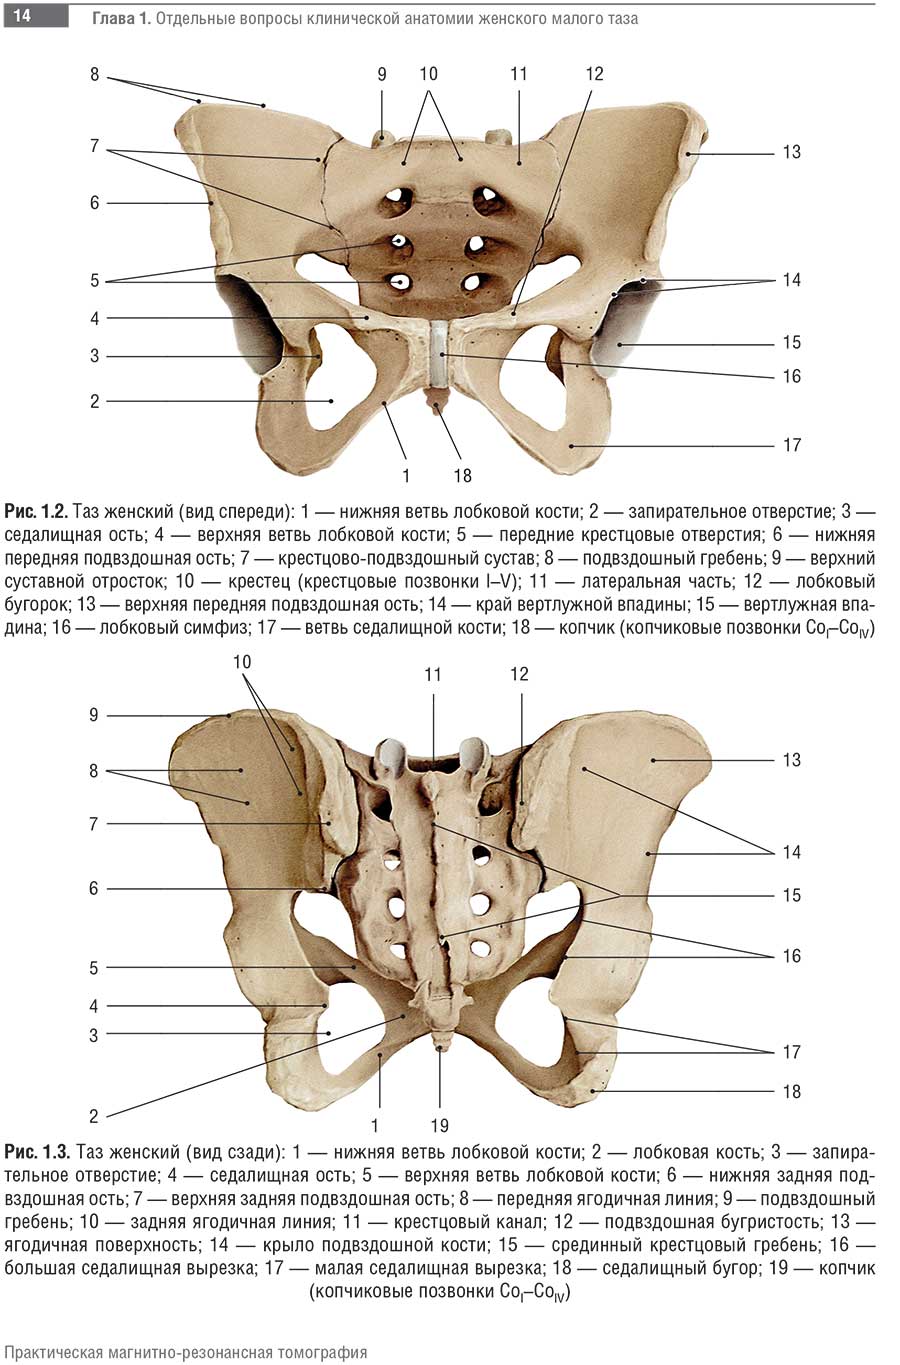

Магнитно-резонансная томография (МРТ) малого таза у женщин является важным методом диагностики различных заболеваний. На фотографиях МРТ можно увидеть органы малого таза, такие как матка, яичники, мочевой пузырь, прямая кишка и другие структуры.

Примеры фото МРТ малого таза у женщин

Ниже представлены примеры фотографий МРТ малого таза у женщин, позволяющие увидеть, как выглядят снимки и какие изменения могут быть обнаружены специалистами.